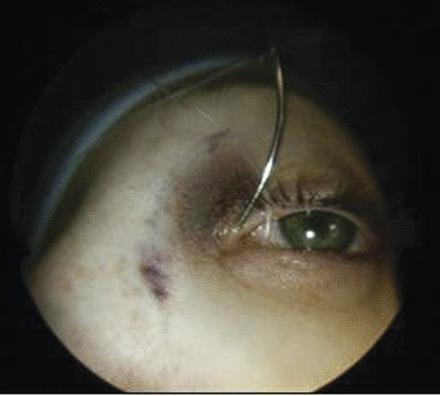

This was an unusual case of lacrimal sac compression by an anterior ethmoidal mucocele presenting as a late complication of a dacryocystorhinostomy (DCR) that was jointly managed by ophthalmic and ENT surgeons via an endoscopic approach. A 22-year-old lady presented with a 12-month history of a painless lump in her left medial canthus area and a 6-month history of left intermittent epiphora. She had a DCR when she was 15 years old with initial symptom control until recent recurrence. There were no nasal or other eye symptoms. The rest of the eye and nasendoscopic examinations were unremarkable. An MRI scan suggested a dacryocystocele; however, a further CT scan revealed a 1.6 cm cystic lesion consistent with an anterior ethmoidal mucocele compressing the lacrimal sac. An endoscopic left anterior ethmoidectomy with marsupialisation of the mucocele was performed in combination with an endoscopic DCR. She made good post-operative recovery.

这是一例不寻常的病例,即筛窦黏液囊肿压迫泪囊,表现为泪囊鼻腔吻合术(DCR)的晚期并发症,由眼科和耳鼻喉科医生通过内镜方法联合处理。一名22岁女性,左侧内眦区出现无痛性肿块12个月,左侧间歇性溢泪6个月。她15岁时接受了DCR,最初症状得到控制,直到最近复发。无鼻部或其他眼部症状。眼部其他检查及鼻内镜检查均无异常。MRI扫描提示泪囊膨出;然而,进一步的CT扫描显示一个1.6 cm的囊性病变,符合筛窦黏液囊肿压迫泪囊。在内镜下行左侧前筛窦切除术并对黏液囊肿进行袋形缝合,同时行内镜下DCR。术后恢复良好。